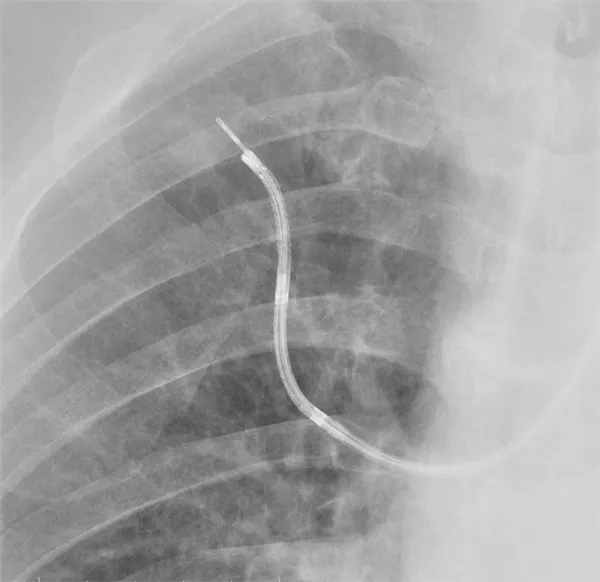

当院では仮想気管支鏡(VBN: Virtual Bronchoscopic Navigation)システム、極細径気管支鏡、ガイドシース気管支腔内超音波断層法(EBUS-GS)システム、超音波気管支鏡ガイド下針生検システム(EBUS-TBNA)、経食道的気管支鏡下穿刺吸引生検法(endoscopic ultrasound with bronchoscope-guided fine-needle aspiration;EUS-B-FNA)等を導入し、それら新しいデバイスの有用性を検討している。

また、近年発達してきた EBUS-GS 法や VBN を使用しても、診断困難な末梢型肺がんは存在する。EBUS-GS 法は、デバイスが病変内に到達したことを確認する優れた方法であるが、気管支内腔に腫瘍が進展していない場合、診断率が低下することが予想される。そこで、気管支鏡検査前に行われた CT や PET 画像などをもとに、診断率を予測する因子を評価し報告した(Umeda Y, et al. Lung Cancer. 2014)。全身状態の悪い症例に対しても、安全に実施可能なEUS-B-FNAの有用性と安全性に関する前向き研究を実施し、治療法決定に必要な遺伝子パネル検査やPD-L1などの免疫染色などの検査に適切な検体を安全に得られることを報告した (Nakashima K, et al. Intern Med. 2021, Nakashima K, et al. BMC Pulm Med. 2023)。さらに現在実施中の試験として、近年進行肺がんの治療方針決定に重要な次世代シーケンサーを用いた遺伝子変異解析が、EBUS-TBNAを用いた細胞診検体で適切に実施可能か検討している。